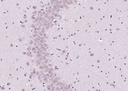

r氨基丁酸抗体

目录号:bs-2252R

商品规格:50ul